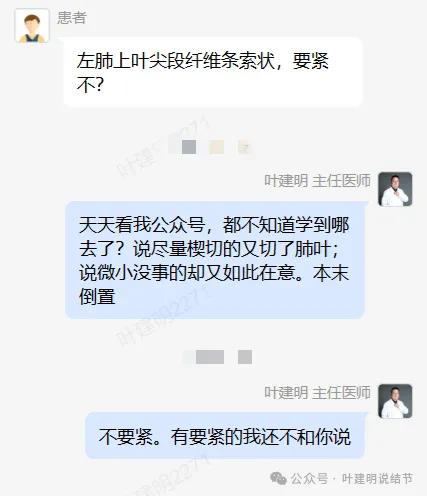

事后证明没有转移,也没有高危亚型,也没有高危因素,而且是实性的随访了3年了,有增大才考虑恶性予以手术的。位置这么边上,多可惜呀!但结友还在纠结咨询“左上叶尖段纤维条索状要不要紧?”。唉!

骂人的心都有了!天天看我公众号,说是学到了很多知识,更能客观淡定对待肺结节资深粉丝。都学到哪儿去了?我说微小不要紧的,又在紧张;我说早期可楔切的,却又切了肺叶!

结友又自己截了处图,微小的结节,问有没有危险。唉,抓重点,抓主要矛盾、抓关键!